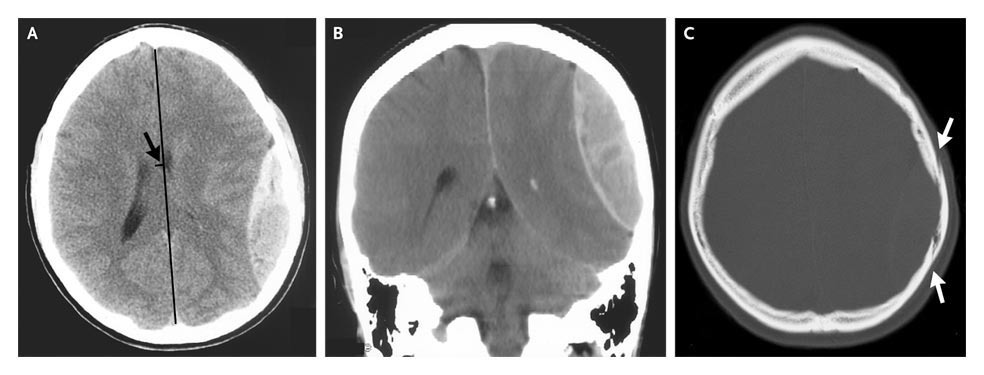

Computed tomography of the head revealed a 2.5-cm epidural hematoma in the left parietal region (Panels A and B) underlying a linear, nondisplaced skull fracture (Panel C, arrows). There was mass effect, effacement of the left ventricular system, and 6 mm of left-to-right midline shift (Panel A, arrow).